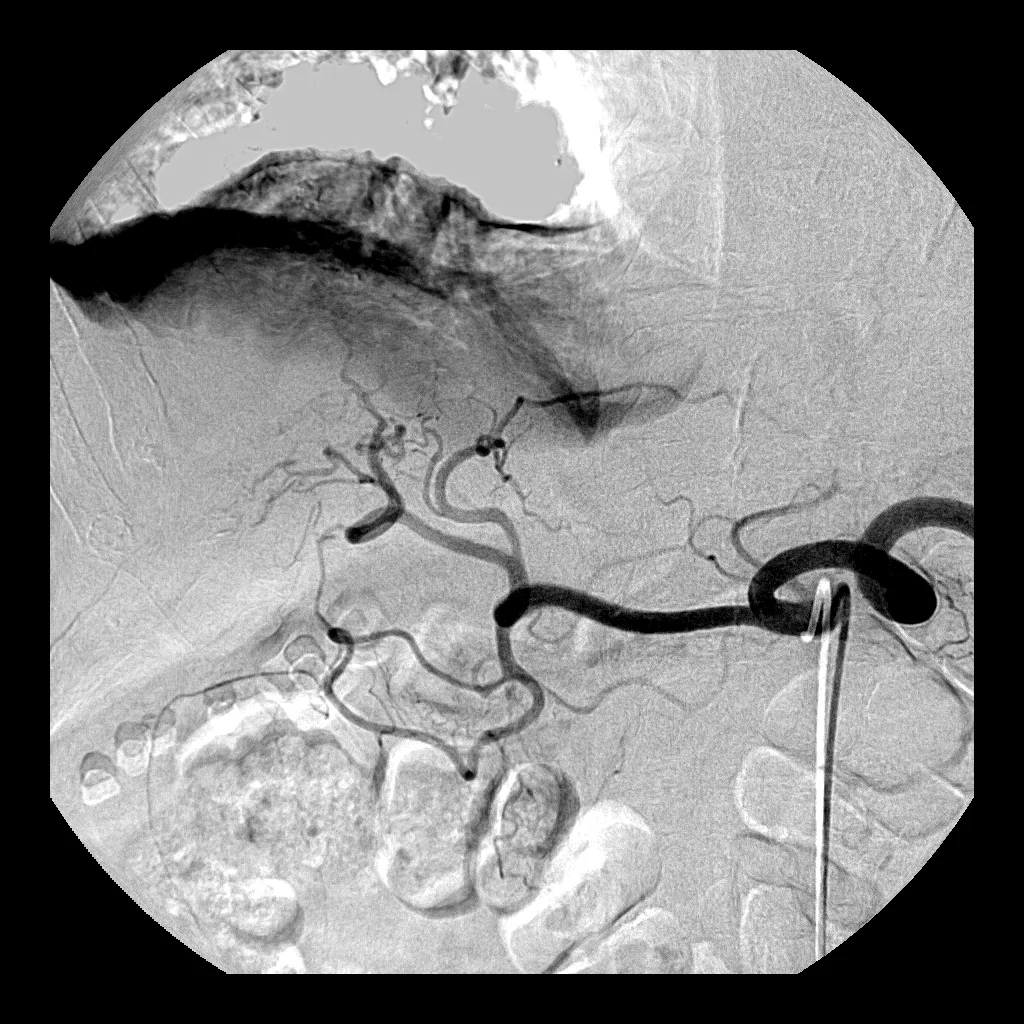

Interventional Oncology: Case 5

71 year old male with HCC who presents for radioembolization.